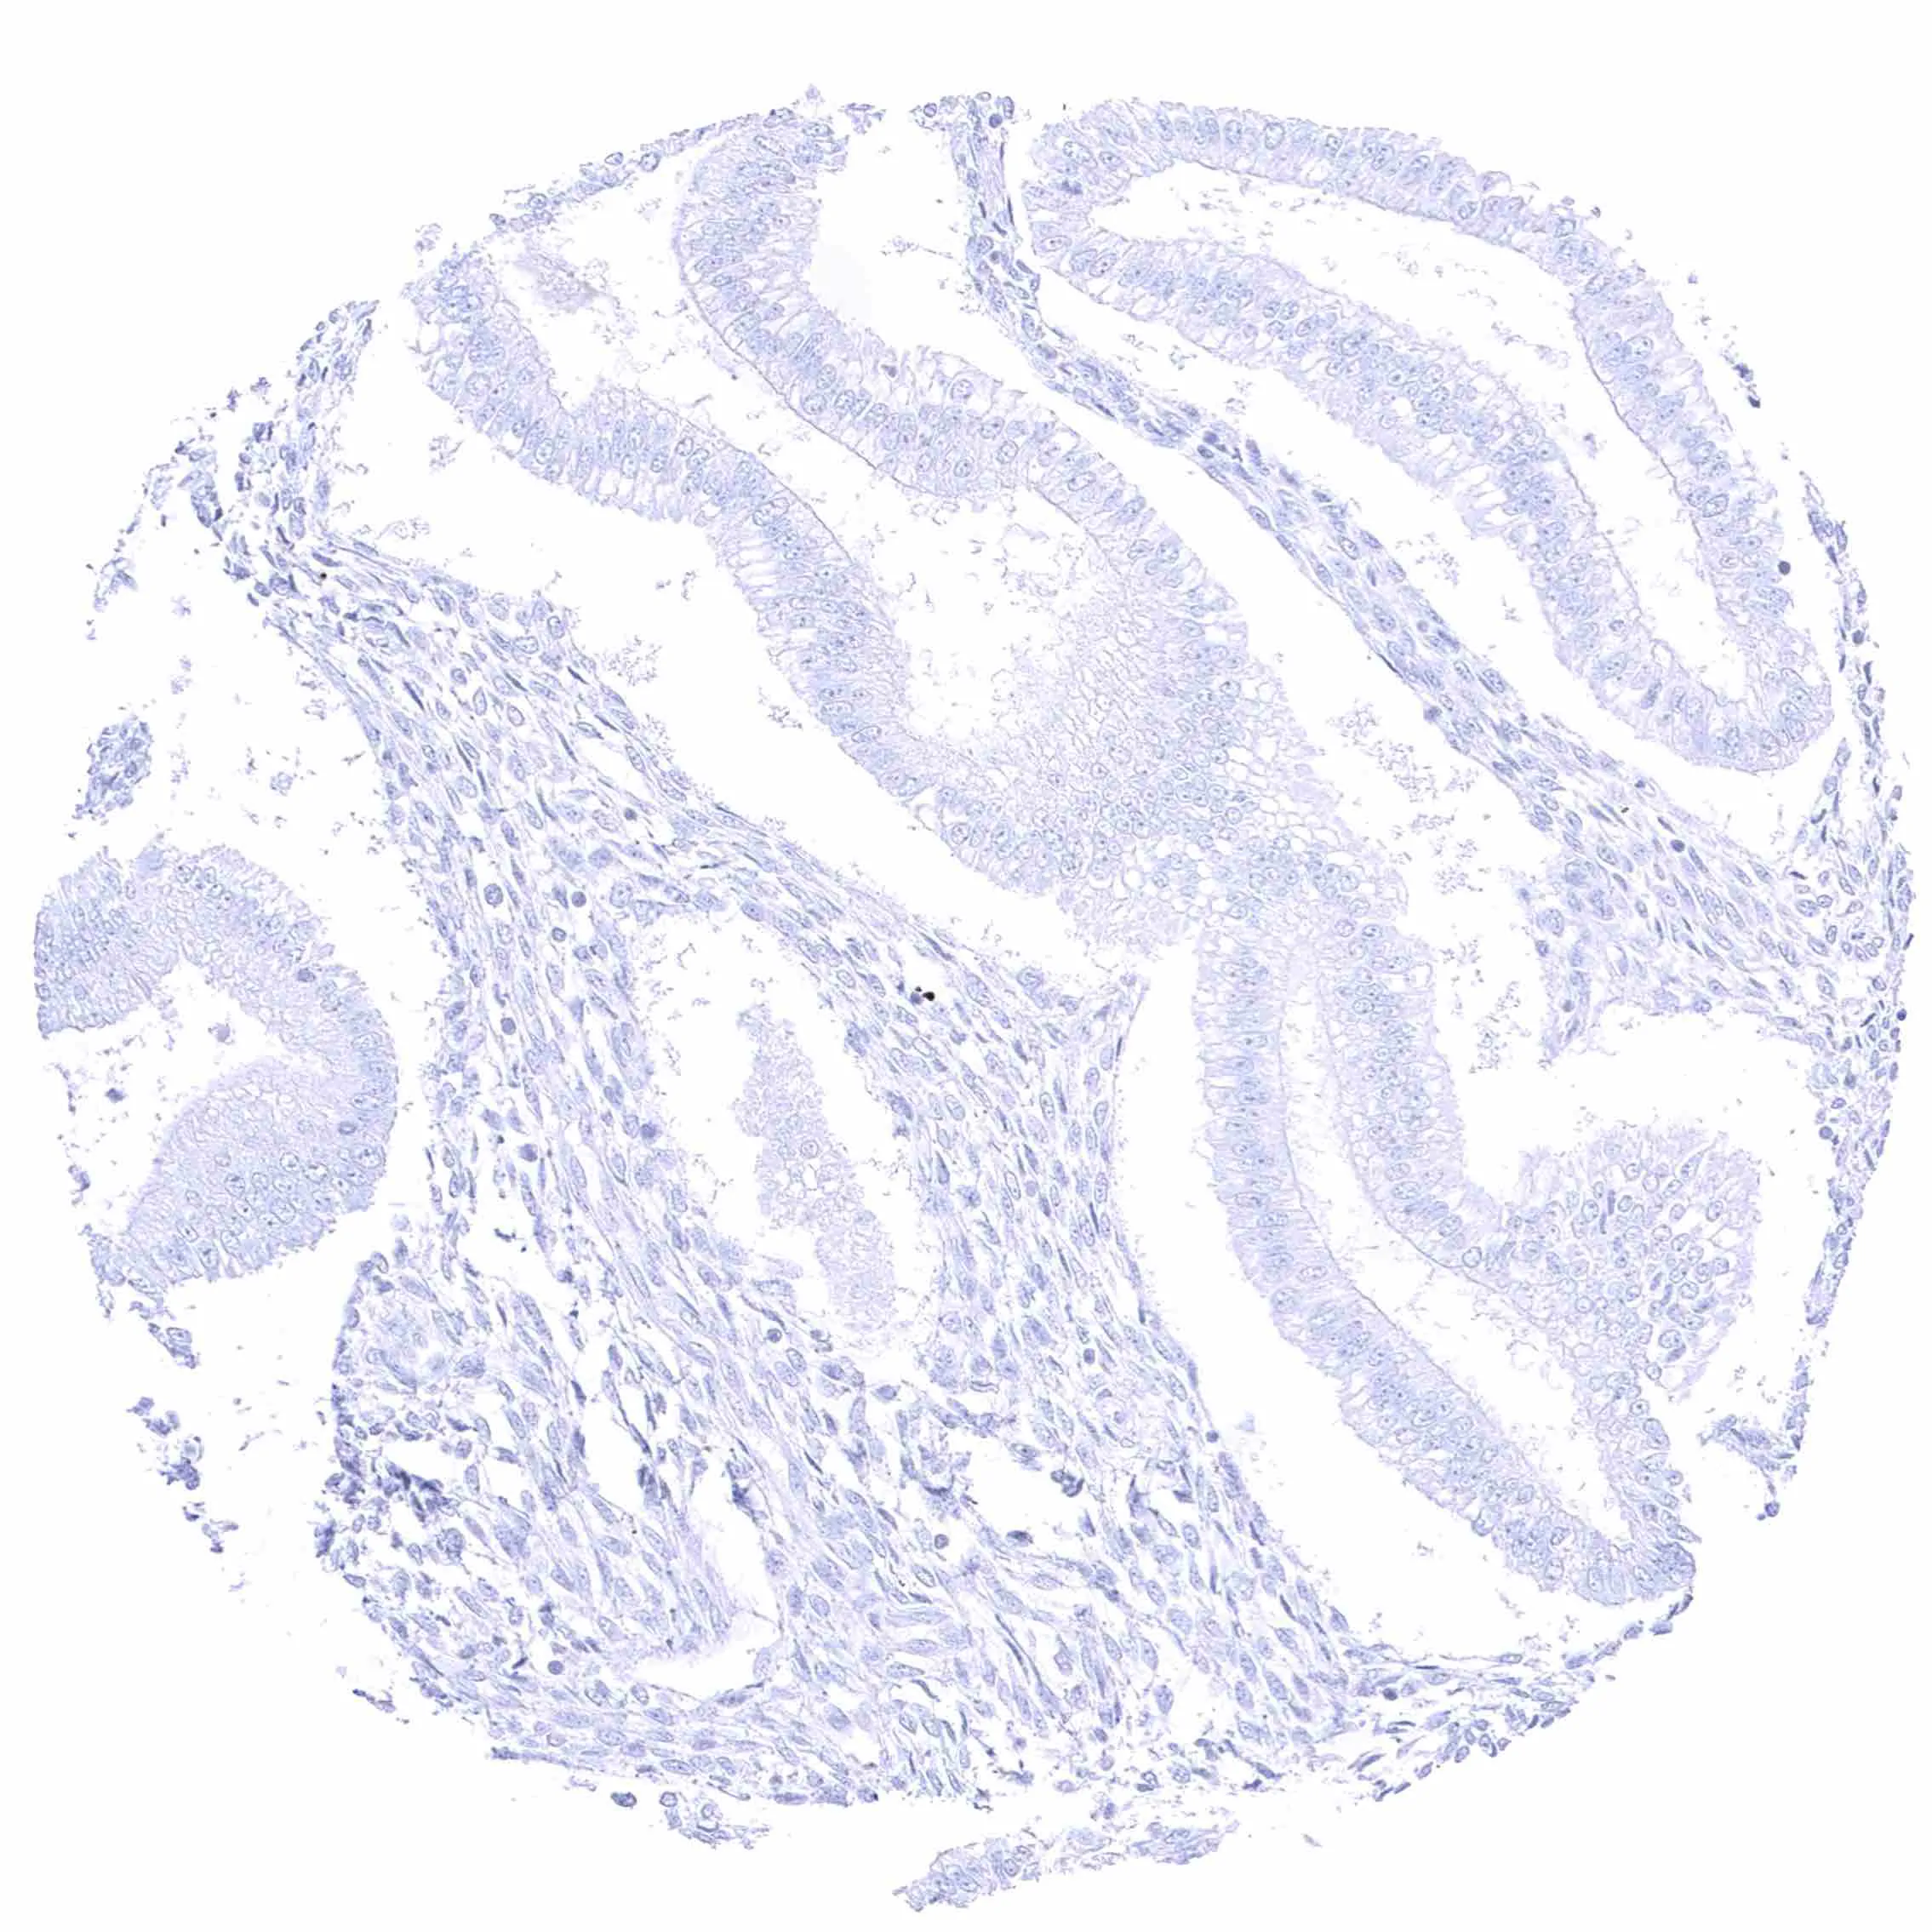

Ileum, mucosa

Duodenum, mucosa

Colon descendens, mucosa